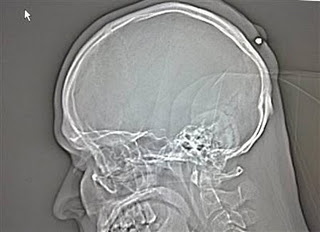

2. Peluru 5 tahun dalam kepala

Seorang pria yang hidup di Jerman hidup dengan normal dan baik-baik saja selama lima tahun tanpa menyadari ia telah ditembak di kepala. Peluru kaliber 0,22 ditemukan ketika orang itu pergi ke dokter untuk memiliki apa yang ia pikir merupakan kista . Yang dia ingat adalah bahwa ia telah menerima pukulan ke kepala sekitar tengah malam di sebuah pesta Tahun Baru  tahun 2004 tapi sudah lupa tentang hal itu karena ia “sangat mabuk.”